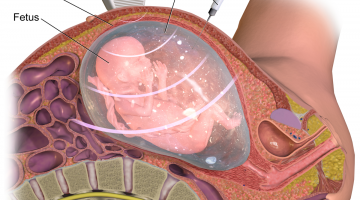

Detailed Scan During Pregnancy

During the 18 – 28 weeks, detailed scan is done to find out if your baby has any adnormal organs or body structure. And we had selected to do our scan in Medipulse Clinic in Bukit Jalil; just not because of pricing but the professional sonographer and doctor there. In here, we had made the appointment a few days before and their sonographer usually will be … [Read more...] about Detailed Scan During Pregnancy